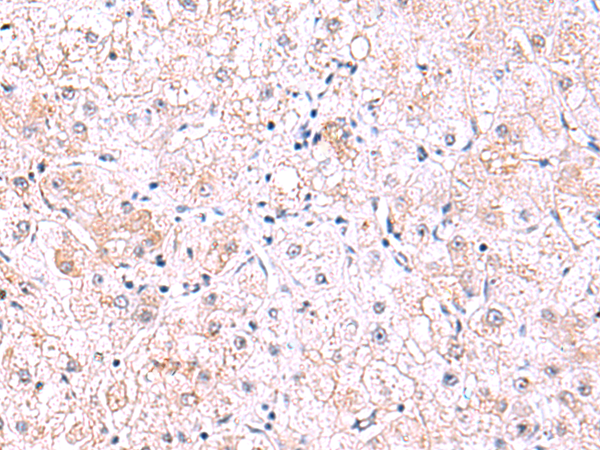

分类: 科研抗体货号: P11032别名: no me应用: IHC反应种属: Human, Mouse